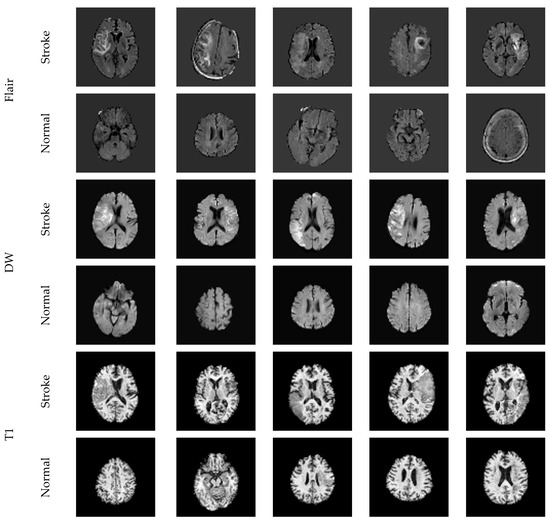

2.2. Image Database

2.3. VGG-SegNet